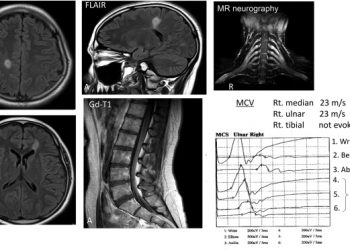

ЧИТАТЬ ВСЕАутоантитела, в частности, против аквапорина-4 и гликопротеина миелин-олигодендроцитов (MOG), помогают в качестве биомаркеров в дифференциальной диагностике демиелинизации. Здесь мы сообщаем об...

ЧИТАТЬ ВСЕОсобенности Антитела против нейрофацина обнаруживаются при рассеянном склерозе и хронической воспалительной демиелинизирующей полирадикулоневропатии. Антитела IgG4 против нейрофасцина связаны с уникальными...

ЧИТАТЬ ВСЕИммунологические аспекты аутоантител, направленных против паранодальных и узловых белков, составляют важную область исследований. Контактин-1 и контактин-1-ассоциированный белок, глиомедин и нейрофасцин (NF)...